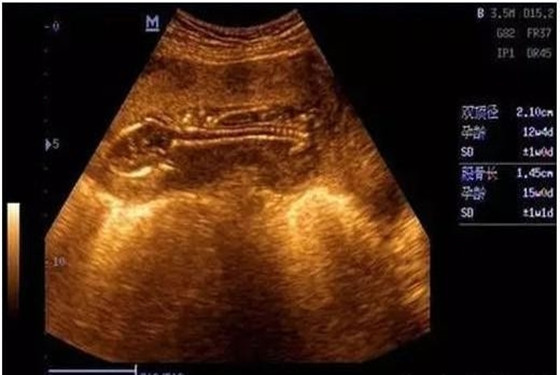

一般来说,B超单上的数据有很多,比如双顶径、腹围、股骨长、胎囊、胎心次数等,还可以从B超中观察到胎盘、羊水、脐带、胎儿脊椎等情况。老一辈有些人的说法认为看怀孕40-50天时的B超单,观察孕囊的大小和形状就能看出胎儿的性别,孕囊形状是椭圆或圆形的是女宝宝,长条形的是男宝宝。

1、7W+1D的BC数据: 胎囊2.9*1.9,生的是男胎儿。

2、60天的BC数据:孕囊大小是3.6*1.6MM,生下的是男胎儿。

3、5W+6D,孕囊:25mm*11mm,是男胎儿。

4、8周多是的BC,胎囊是19MM*10MM,后来BC照出来也是男胎儿。

通过B超数据如何看男孩 揭秘九个最准怀男孩征兆

5、62天,内见孕囊2.6*1.8,生的是可爱的男胎儿。

6、孕囊33*18 现B超是男胎儿。

7、孕囊长为44*20mm,生的是男胎儿。

8、9周+6天BC结果5.6*2.4 23周+5天BC看出是男胎儿。

9、7周多的B超数据,宫内见3.8*2.3CM妊娠囊,生的是男胎儿。

10、3.3*2.0cm生的是可爱的男胎儿。